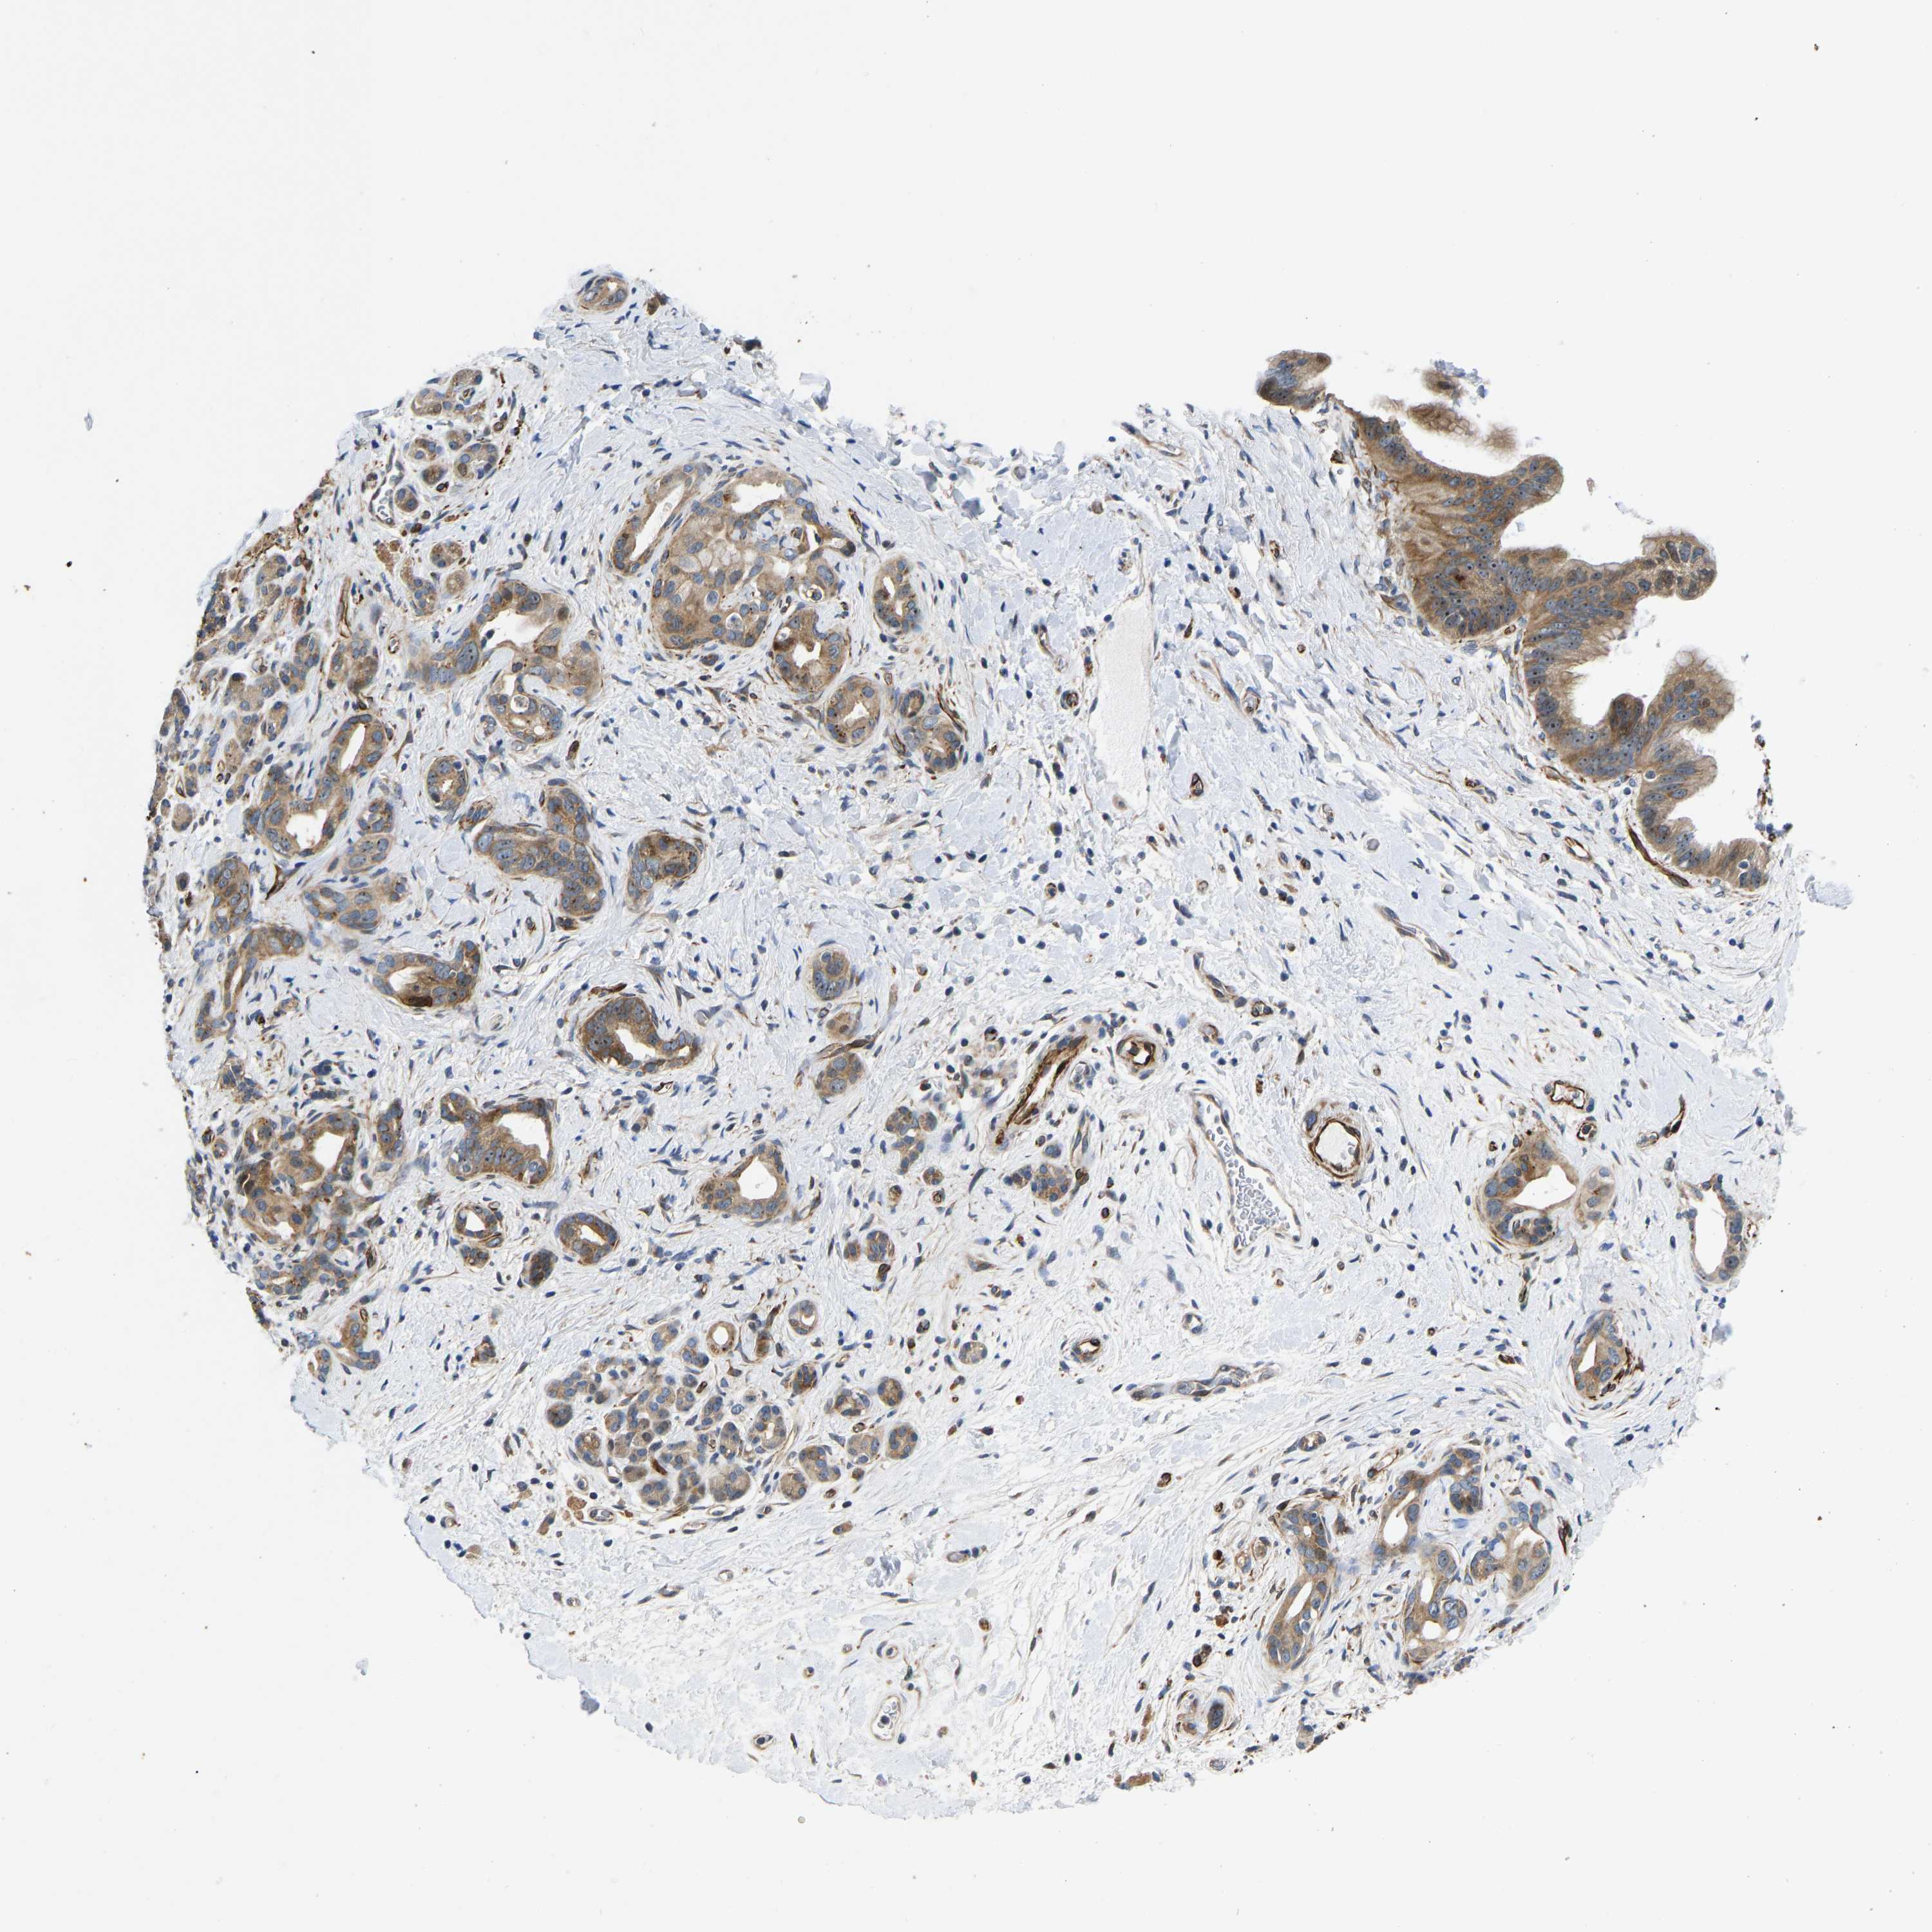

PANCREATIC CANCER - Protein expressioni

A mouse-over function shows sample information and annotation data. Click on an image to view it in a full screen mode. Samples can be filtered based on level of antibody staining by selecting one or several of the following categories: high, medium, low and not detected. The assay and annotation is described here.

Note that samples used for immunohistochemistry by the Human Protein Atlas do not correspond to samples in the TCGA dataset.

Antibody stainingi

Antibody staining in the annotated cell types in the current human tissue is reported as not detected, low, medium, or high, based on conventional immunohistochemistry profiling in selected tissues. This score is based on the combination of the staining intensity and fraction of stained cells.

Each image is clickable and will lead to virtual microscopy that enables deeper exploration of all samples and also displays staining intensity scores, fraction scores and subcellular localization as well as patient and tissue information for each sample.

Antibody HPA013816

Antibody HPA015622

Staining

High

Medium

Low

Not detected

Intensity

Strong

Moderate

Weak

Negative

Quantity

>75%

75%-25%

<25%

None

Location

Nuclear

Cytoplasmic/membranous

Cytoplasmic/membranous,nuclear

Adenocarcinoma, NOS